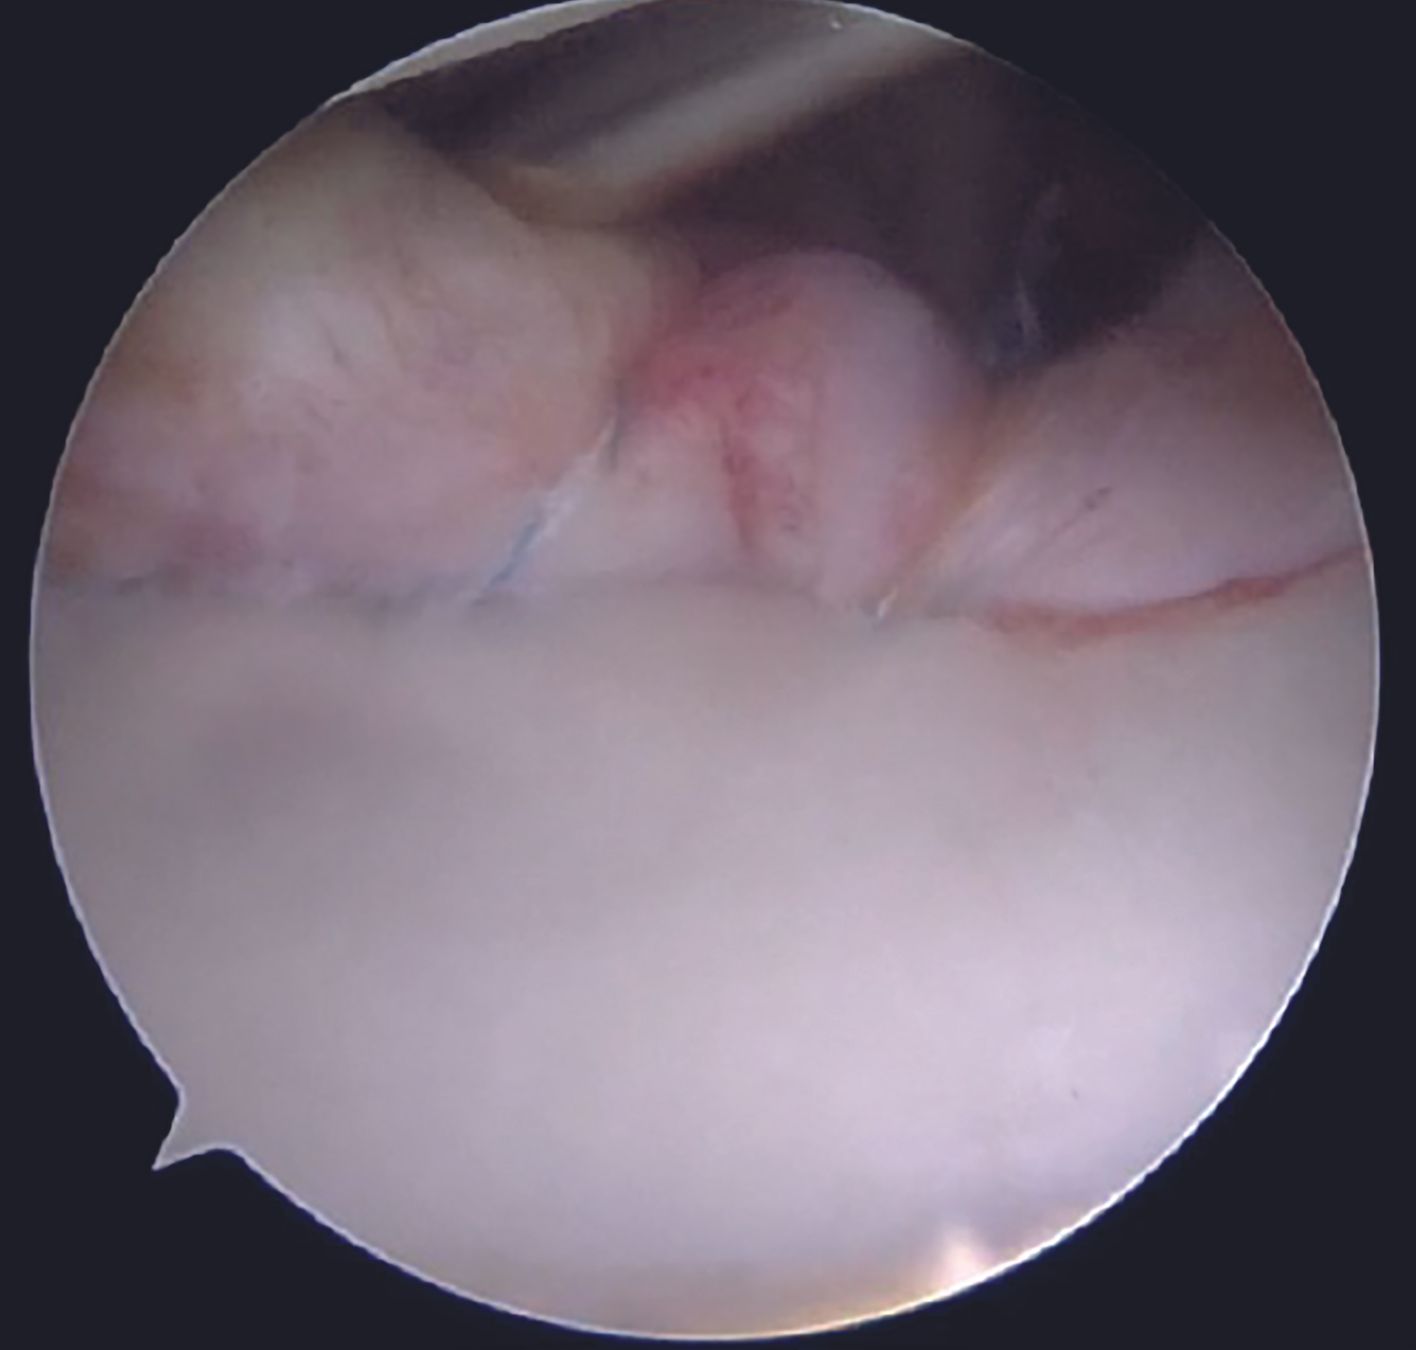

Care is taken to keep the knots away from the face of the glenoid by using the shuttled tape as a post and the other one as a throw. Before tying the sliding knot, utmost attention should be paid to provide adequate tension to the labral tissue by pulling the labrum superiorly with a grasper. Tapes are cut with an arthroscopic cutter around 4 to 5mm distal to the knot. One anchor each is placed at 4 and then at 3 O'clock position following a similar steps. After completion of the repair (Figure 15, 16), its integrity and stability is confirmed with a probe. After a thorough wash, closure is done with mattress sutures using 3-0 Ethilon.

Anterior instability of shoulder is a frequently encountered pathology in day to day clinical practice. Multiple factors play a role in deciding the modality of treatment including the extent of glenoid bone loss, patient's age, level of physical activity, involvement in a contact or overhead sport and potential compliance to rehabilitation. Soft tissue Bankart repair aims to restore the anatomy, thus imparting the native stability to the joint. Success of the procedure depends on the anatomical healing of the labrum, anchors being only a tool for the repair.